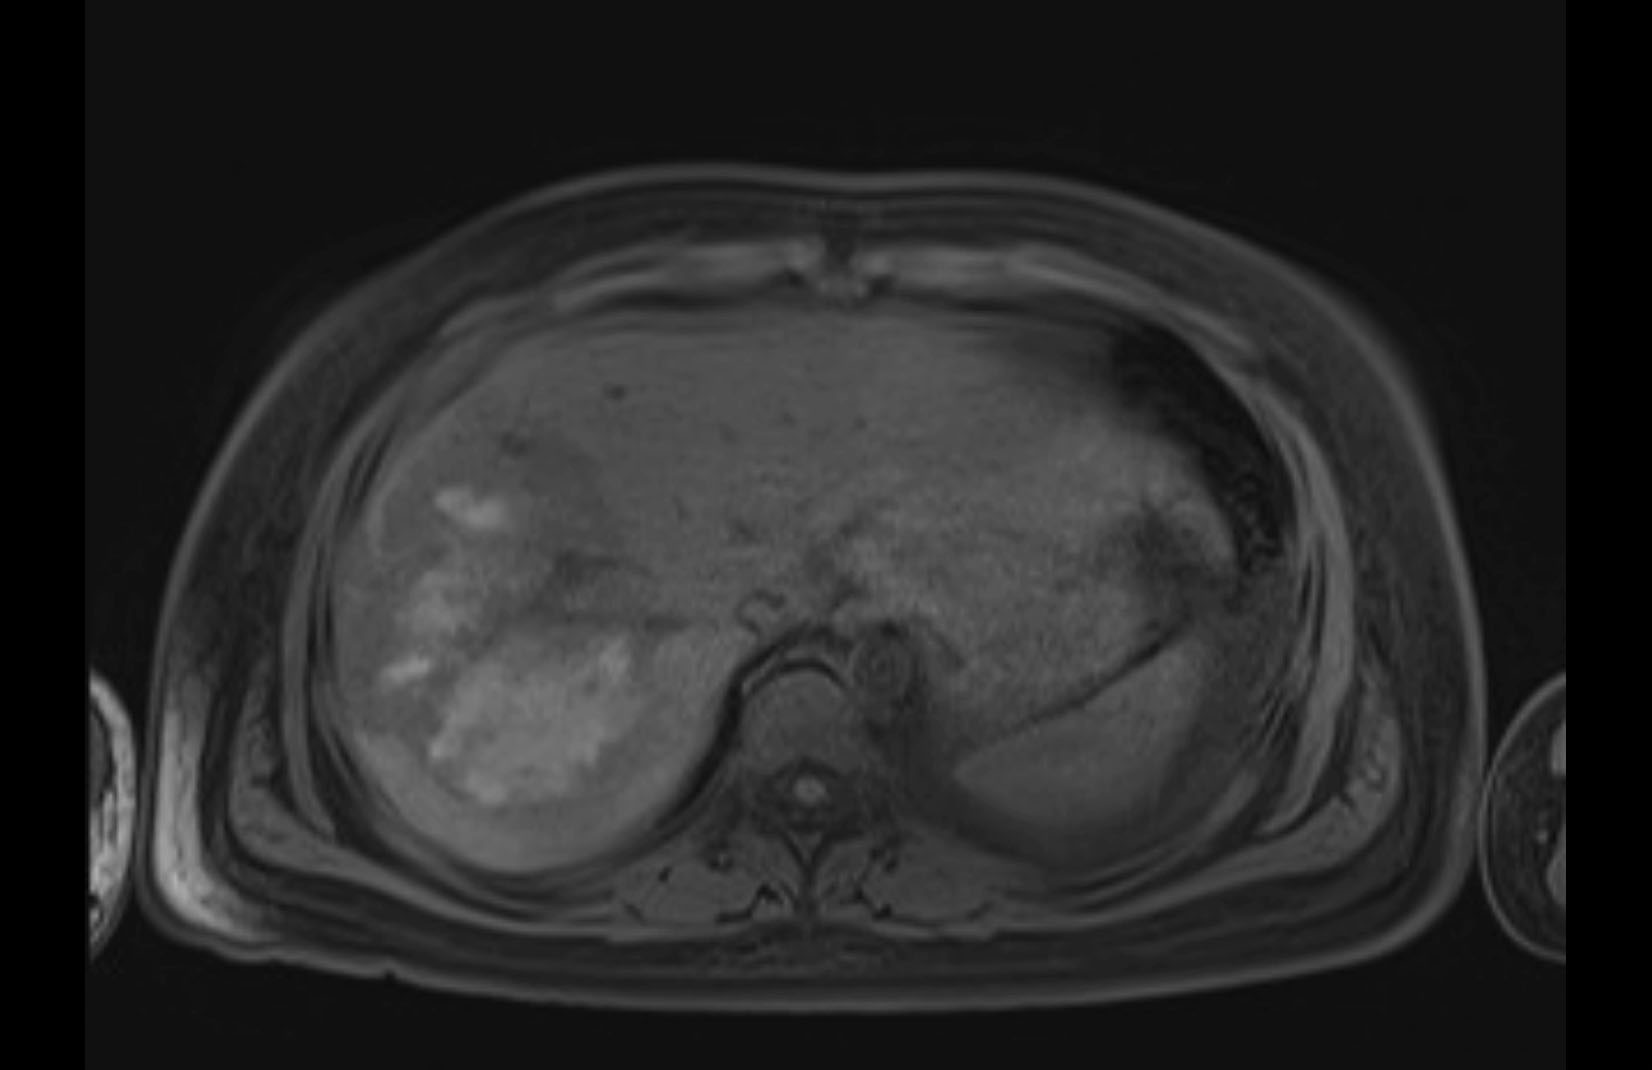

Imaging Analysis

Look through the patient's CT scan to identify any areas of concern for the necessary procedure.

MRI T1

Based on initial findings, which issue(s) would you be most concerned about?